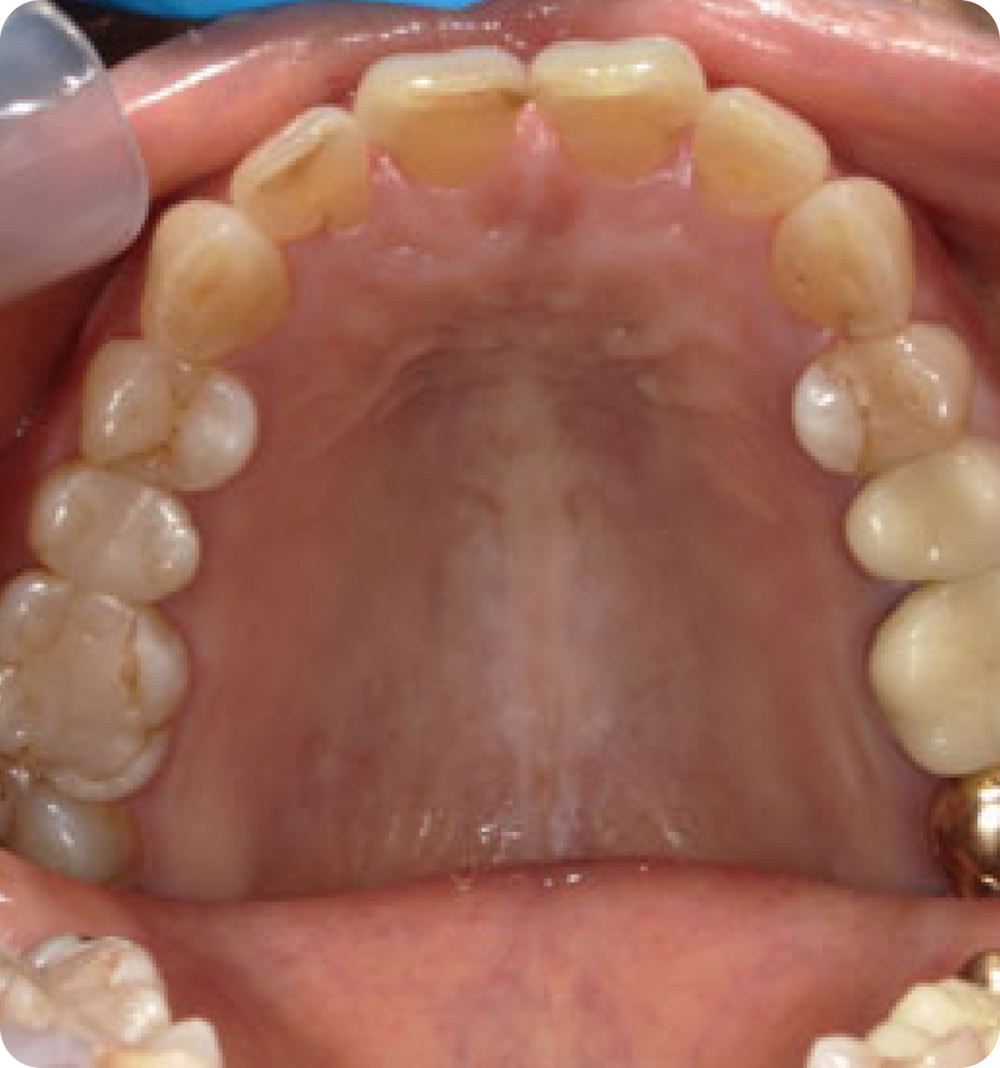

マウスピース矯正症例 術中

術中

年齢 70代(女性)

主訴 上の歯ならびがガタガタなのが気になる

期間・費用 上顎のみ8か月 264,000円(税込)